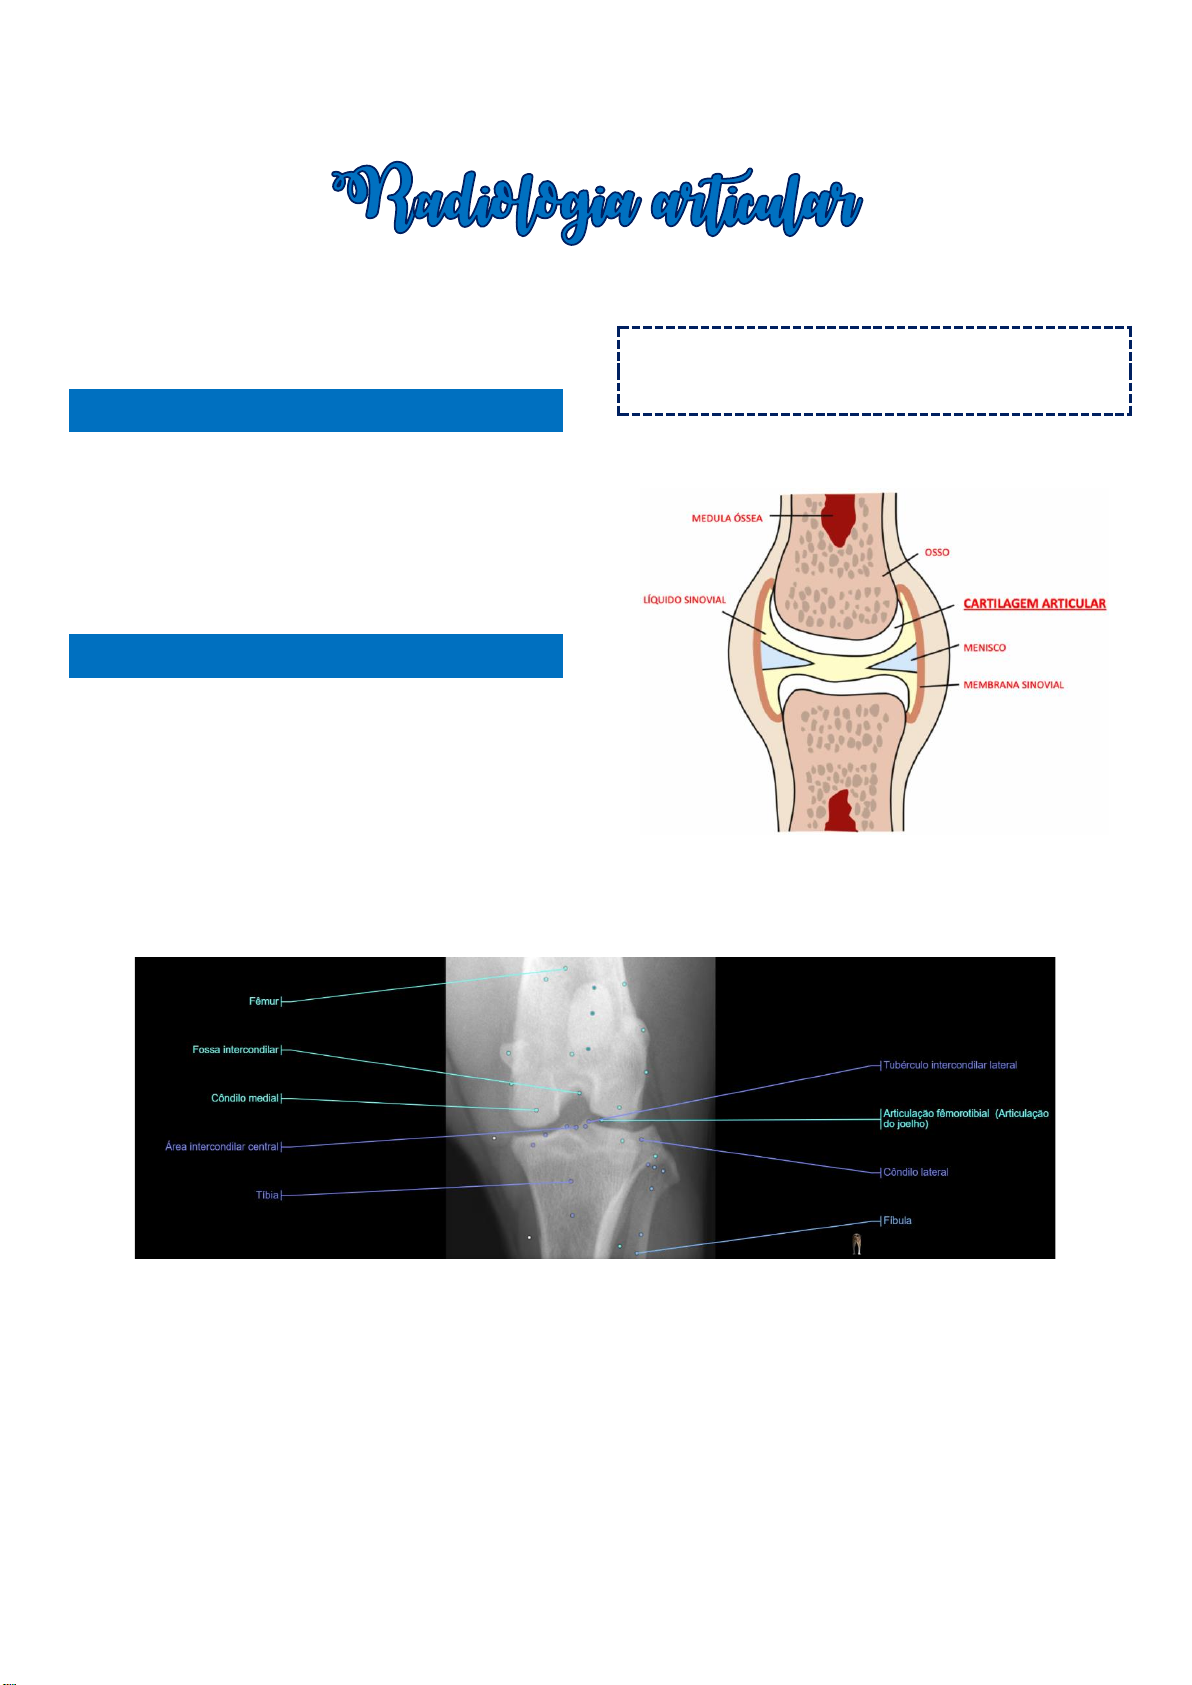

Figura 1 - composição da articulação sinovial.

Figura 2 – principais componentes da articulação do joelho esquerdo de um cão, projeção craniocaudal.